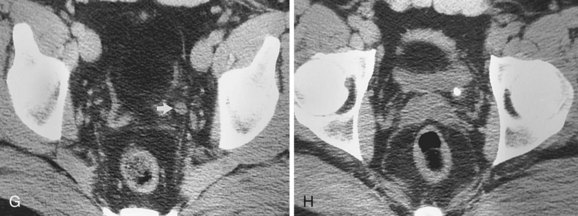

The patient is positioned supine. An abdominal plain radiograph is obtained before the introduction of contrast material (Fig. 4–8A). A commonly employed technique is to insert a small-gauge catheter into the ostomy of the loop, advancing it just proximal to the abdominal wall fascia. The balloon on such a catheter can then be inflated to 5 to 10 mL with sterile water. By gently introducing contrast through the catheter, the loop can be distended, usually producing bilateral reflux into the upper tracts. Oblique films should be obtained in order to evaluate the entire length of the loop (Fig. 4–8B). Because of the angle at which many loops are constructed, a traditional anteroposterior (AP) view will often show a foreshortened loop and could miss a substantial pathology. A drain film should be obtained (Fig. 4–8C). This may demonstrate whether there is obstruction of the conduit.

Figure 4–8 Loopography in a patient with epispadias/exstrophy and ileal conduit urinary diversion. The plain film (A) shows wide diastasis of the pubic symphysis. After contrast administration via a catheter placed in the ileal conduit, free reflux of both ureterointestinal anastomoses is demonstrated (B). A postdrain radiograph (C) demonstrates persistent dilation of the proximal loop indicating mechanical obstruction of the conduit (arrows).